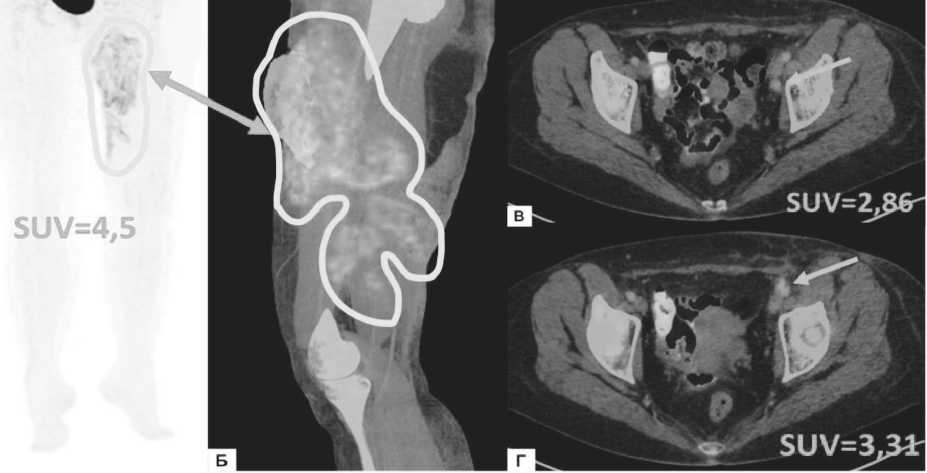

С целью оценки распространённости заболева ния пациентке было выполнено ПЭТ / КТ всего тела с 18F- ФДГ , по результатам которого , в мягких тканях по медиальной поверхности левого бедра определялся крупный участок неравномерного уплотнения кожи и подкожной жировой клетчатки неправильной фор -

Рисунок 2. ПЭТ/КТ с ISF-ФДГ ПЭТ-изображение, фронтальная проекция (А), совмещенное ПЭТ/КТ-изображение, сагиттальная проекция в режиме многослойного изображения (Б), совмещенные ПЭТ/ КТ-изображения, аксиальные проекции (В, Г). Массивное метаболически активное образование кожи медиальной поверхности левого бедра (обведено белым цветом и отмечено стрелкой), единичные наружные подвздошные лимфоузлы слева с повышенным уровнем гликолитической активности (отмечены белыми стрелками)

мы приблизительными размерами 289×117×146 мм , с накоплением радиофармпрепарата по периферии зоны поражения SUV=12,6. При этом в центральных отделах дефекта кожного покрова ( в верхней трети левого бедра ) определялась зона аметаболизма , обу словленная некрозом тканей . Также были выявлены единичные метаболически активные парааорталь - ные , тазовые и паховые лимфоузлы слева (SUV=3,4), референсные значения SUV в пуле крови – 1,6, в пече ни - 2,6. ( Рисунок 2).